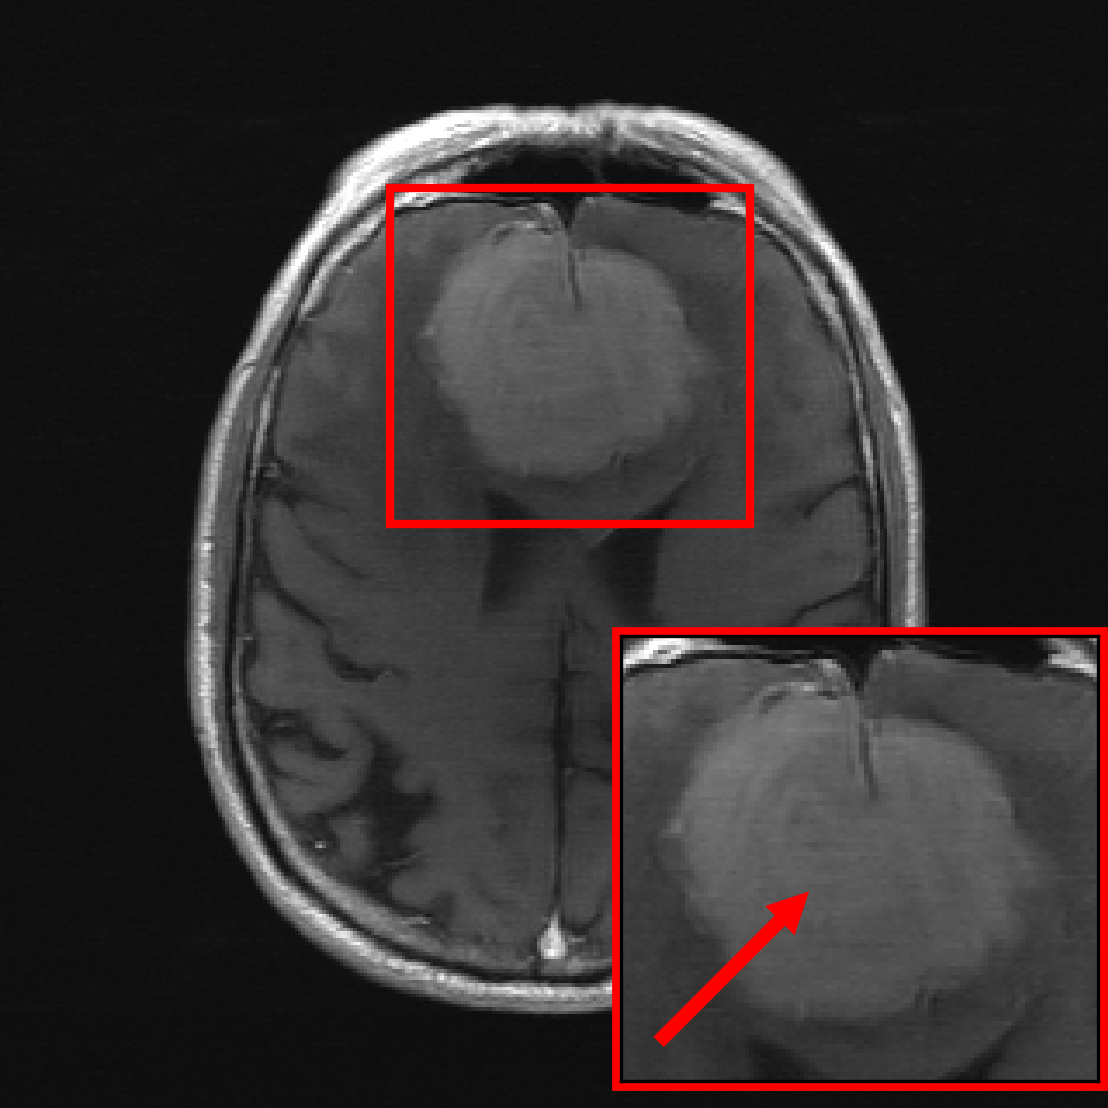

Figure 7 shows the models’ performance on relative to their performance on . Reconstructions are evaluated only on the region containing the pathology, where we distinguish between small pathologies ( of the total image size) and large pathologies ( of the total image size) to see potential dependencies on the size of the pathology.

We see that the models trained on show essentially the same performance (SSIM) as models trained on regardless of pathology size. The results indicate that models trained on images without pathologies can reconstruct pathologies as accurately as models trained on images with pathologies. This is further illustrated in Figure 8, where we show reconstructions given by the VarNet of images with a pathology: The model recovers the pathology well even though no pathologies are in the training set. We provide additional results, reconstruction examples, and discussion in Appendix E, including a more nuanced evaluation of the SSIM values for VarNet (Figure 16).